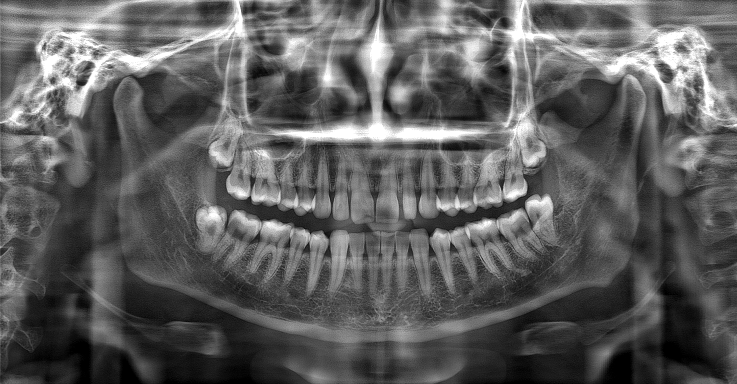

Currently, in pursuit of visual "quality perception," some dental CBCT brands may highlight image clarity by modifying contrast and sharpening, but this can distort and lose detailed information in the image, similar to the excessive smoothing and beautification effects seen in photo editing software. This, in turn, affects the accuracy of the doctor's diagnosis.

Meyer adheres to the core of diagnostic and treatment needs, deeply integrating technological innovation with it, and providing clinical services with real and reliable images. The newly introduced "PD" technology can intelligently adjust various parameters through adaptive capability and, based on a large number of shooting results for verification, give the images a "natural texture" effect. It effectively addresses the challenge of noise reduction obscuring minor lesions and provides clearer restoration of bone and soft tissue structure details.

▲Advantages of "PD" Technology: Deep Restoration of Image Details